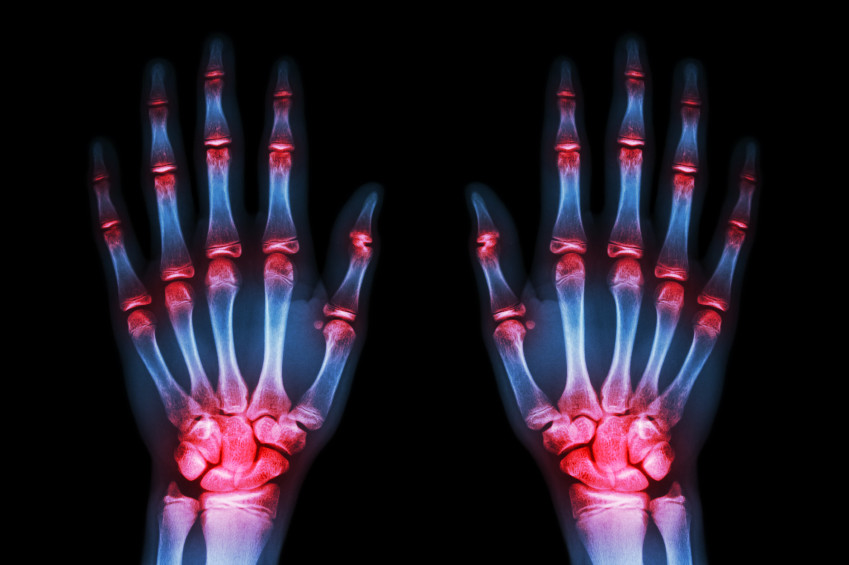

La artritis suele presentante en las pequeñas articulaciones, como las que corresponden a la muñeca de la mano o a los dedos, aunque no es infrecuente que pueda aparecer en otros lugares, causando rigidez, dolor y finalmente, deformidad en las articulaciones afectadas, lo que limita en gran medida la posibilidad de movilización de la persona.

Lo interesante de esta dolencia es que se presenta de manera simétrica, esto quiere decir que si se presenta en la articulación de la muñeca derecha, muy pronto sino es que ya, se manifestará en la muñeca izquierda, y es común que afecta a varias articulaciones al mismo tiempo.